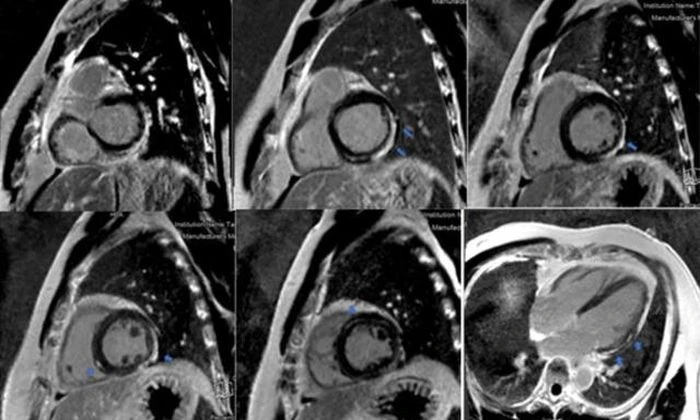

Chụp cộng hưởng từ tim (MRI) giúp phát hiện vùng viêm, phù hoặc hoại tử cơ tim phương pháp không xâm lấn nhưng rất giá trị trong đánh giá mức độ tổn thương.

Hình ảnh MRI tim cho thấy vùng cơ tim bị viêm và tổn thương do phản ứng miễn dịch.